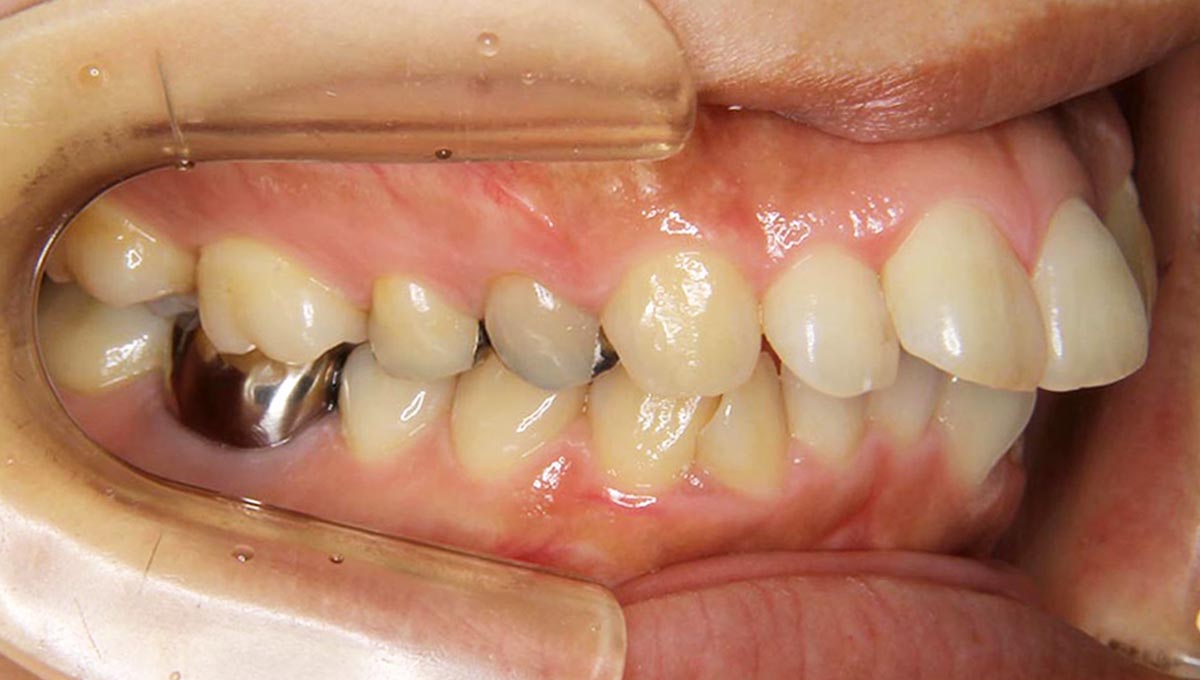

上顎前突(出っ歯)症例

●主訴

出っ歯が気になる

●診断

AngleⅠ級・前歯部叢生

●治療に用いた主な装置

上顎にリンガルブラケット矯正装置、下顎にマルチブラケット装置(ハーフリンガル)

●抜歯部位

上顎左右第一小臼歯2本下顎小臼歯1本

●治療期間

2年1ヶ月

●治療費用

約111万円(ともに税込、調整費、保定費まで含む総額制)

●付記

リスクとして、

①歯根吸収…今回は全くありませんでした。

②カリエス(むし歯)…今回は治療途中でむし歯治療を行いました。